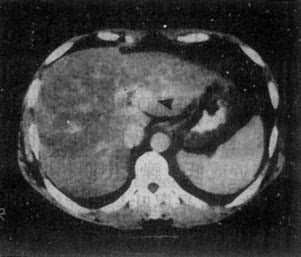

图4-3-5 原发性肝癌

CT增强扫描,肝右叶有一较大圆形低密度肿块(↓),其边缘

部可见多个较密度的强化结节,其强化程度不如正常肝,中

心部仍为未强化的低密度区